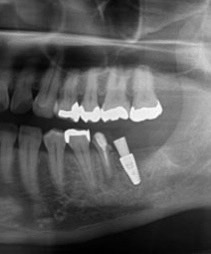

After

こちらが最終的な歯が入った時のレントゲンです。

歯が半分なので本来の大臼歯(奥歯)に比べて小さくします。そうすることによって根の負担を減らし、歯が折れたりしないようにします。

インプラントの被せ物は上の歯と噛み合うように少し右側に大きくなっているのが分かりますでしょうか。